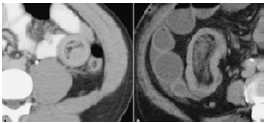

Diffuse wall edema of the transverse ascending colon and splenic angle, image of invaginated appearance and space-occupying lesion at this level can be observed in abdomen and pelvis tomography (Figures 3 and 4).

A. Sausage pattern with alternate areas of low and high attenuation. B. Intraluminal lesion as the lead point of intussusception.

Figura 4: A. Sausage pattern with alternate areas of low and high attenuation. B. Intraluminal lesion as the lead point of intussusception.

Source: Document obtained during the study.

Pathognomonic findings in tomography include bowel thinning, space-occupying lesion and an area of fat and vessel hyperdensity. The computed tomography (CT) performed on the reported patient showed diffuse edema of the transverse ascending colon wall and splenic angle, image of invaginated aspect and space-occupying lesion. 24 Nuclear Magnetic Resonance Morphology is similar to CT and consistent with other studies. 25